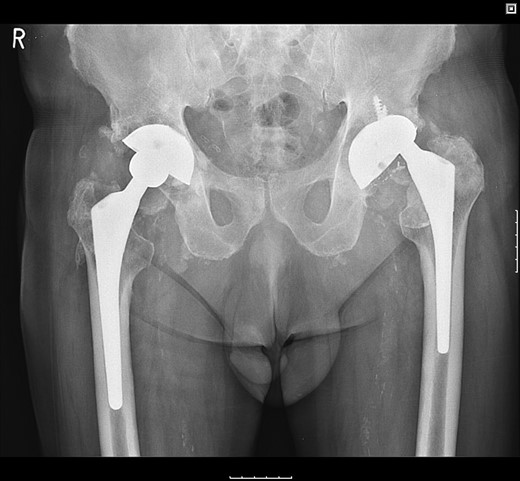

Postoperatively, the patient fell on the ward resulting in posterior dislocation (Fig. 5) requiring an open reduction. Subsequently, the patient developed a superficial surgical site infection, which resolved with antibiotic therapy. Three months following discharge, the patient was pain-free and could ambulate with a Zimmer frame.

Radiograph following postoperative fall demonstrating posterior dislocation.